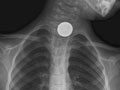

Your doctor may recommend tests such as an X-ray, endoscopy, or barium swallow. These tests can help find the object if it doesn't come out in the stool or if an inhaled object isn't coughed out. A special metal detector might be used. It can help locate a metal object, such as a coin, inside the body. Your doctor may then recommend a procedure to remove the object. Or your doctor may encourage you to keep checking the stool to be sure the object passes out of the body.